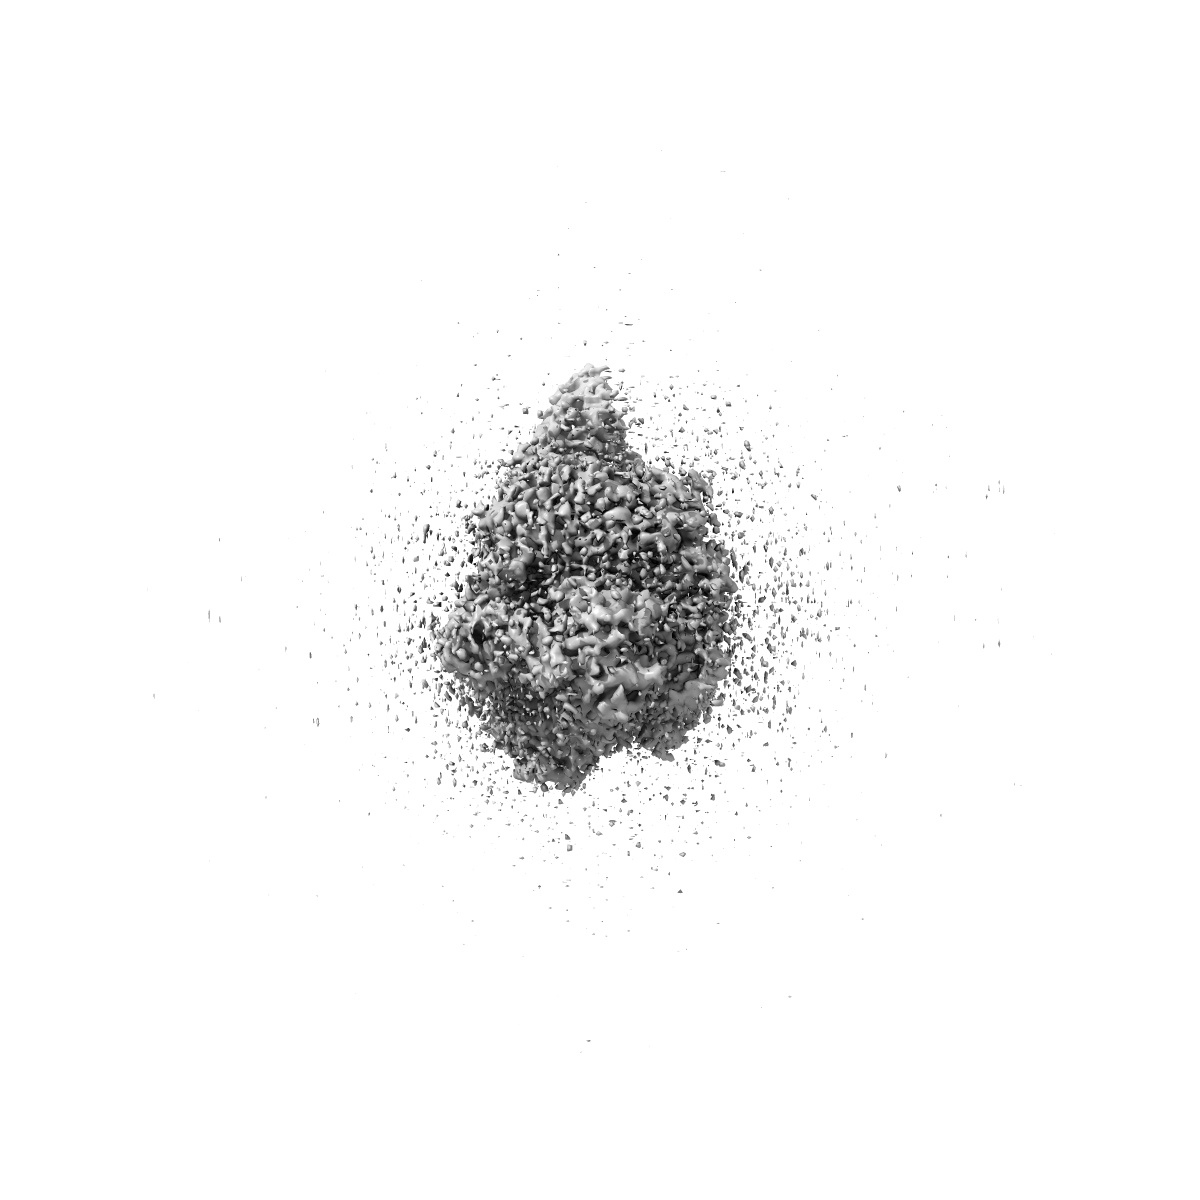

Cryo-EM structure of cancer-specific PI3Kalpha mutant H1047R in complex with BYL-719

Single-particle2.73 Å

Sample: Human PI3Kalpha mutant H1047R in complex with BYL-719